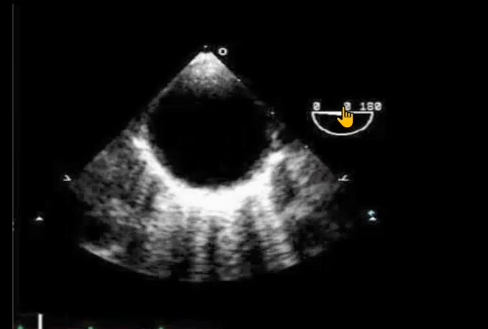

A

Mid esophageal AV long axis view

120- 140 degree (same as Lv long axis)